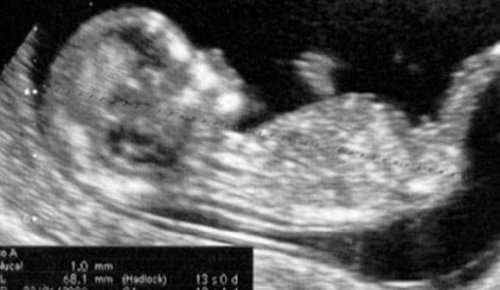

임신 초기가 끝날 무렵에 하는 초음파 검사를 아직 하지 않았다면, 임신 13주차에 할 수 있다. 처음에 임신 확정 후에 해야 하는 일련의 정기 검사 중 마지막 단계이다. 임신 초기에 대한 평가를 마무리하는 시점이 된다.